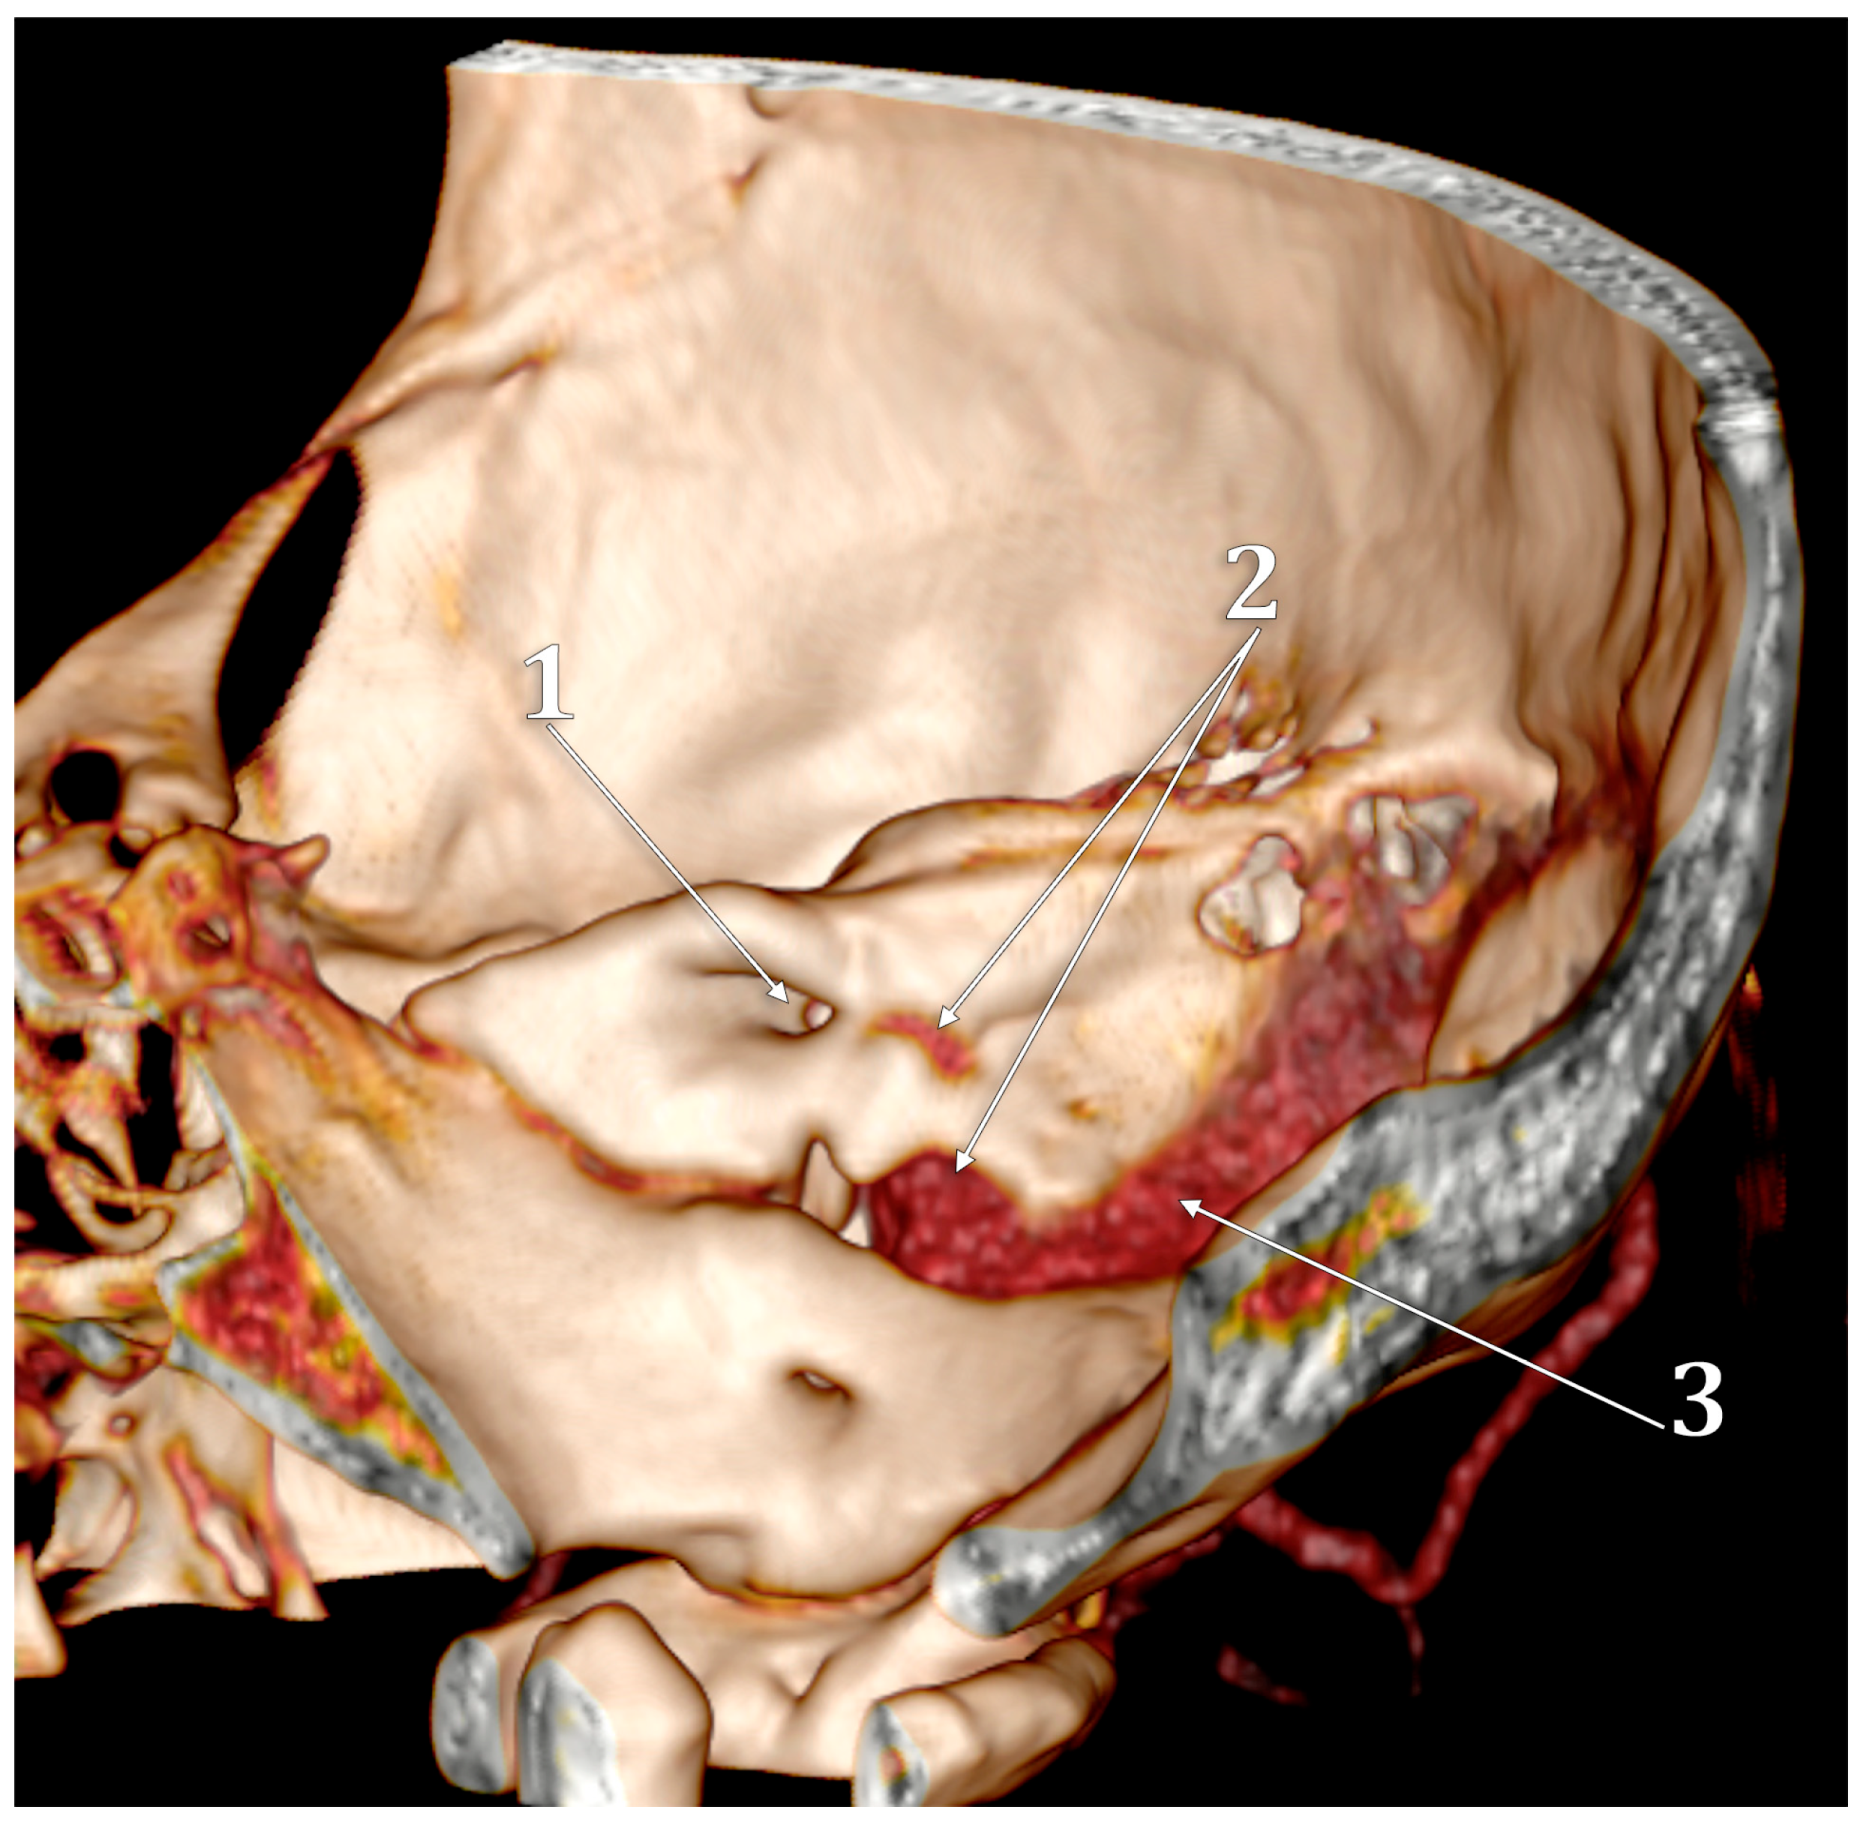

- Raghuram, K.; Cure, J.K.; Harnsberger, H.R. Condylar jugular diverticulum. J. Comput. Assist. Tomogr. 2009, 33, 309–311. [Google Scholar] [CrossRef]

- Jagtap, R.; Wazzan, T.; Hansen, M.; Kashtwari, D. Condylar jugular diverticulum: A report of 3 cases. Imaging Sci. Dent. 2019, 49, 251–256. [Google Scholar] [CrossRef]

- Parillo, M.; Vaccarino, F.; Mallio, C.A.; Quattrocchi, C.C. Right Condylar Jugular Diverticulum: Contrast-enhanced Computed Tomography Findings of a Rare Anatomical Variant of Jugular Bulb. Indian J. Otolaryngol. Head Neck Surg. 2023, 75, 2257–2259. [Google Scholar] [CrossRef] [PubMed]